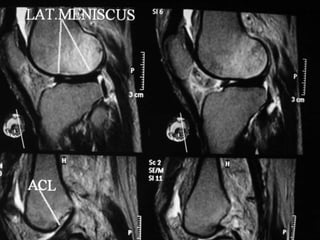

The document presents a detailed case study of a patient with transient osteoporosis of the hip (TOH) and spontaneous osteonecrosis of the knee (SONK) treated at Choithram Hospital & Research Centre in India. Over 20 years, the patient experienced multiple episodes of TOH and SONK with no history of trauma or co-morbidities, resulting in resolutions and recurrences of conditions. The information is intended for orthopedic surgery students and highlights personal experiences and case collections, with a disclaimer regarding content usage and potential controversies.